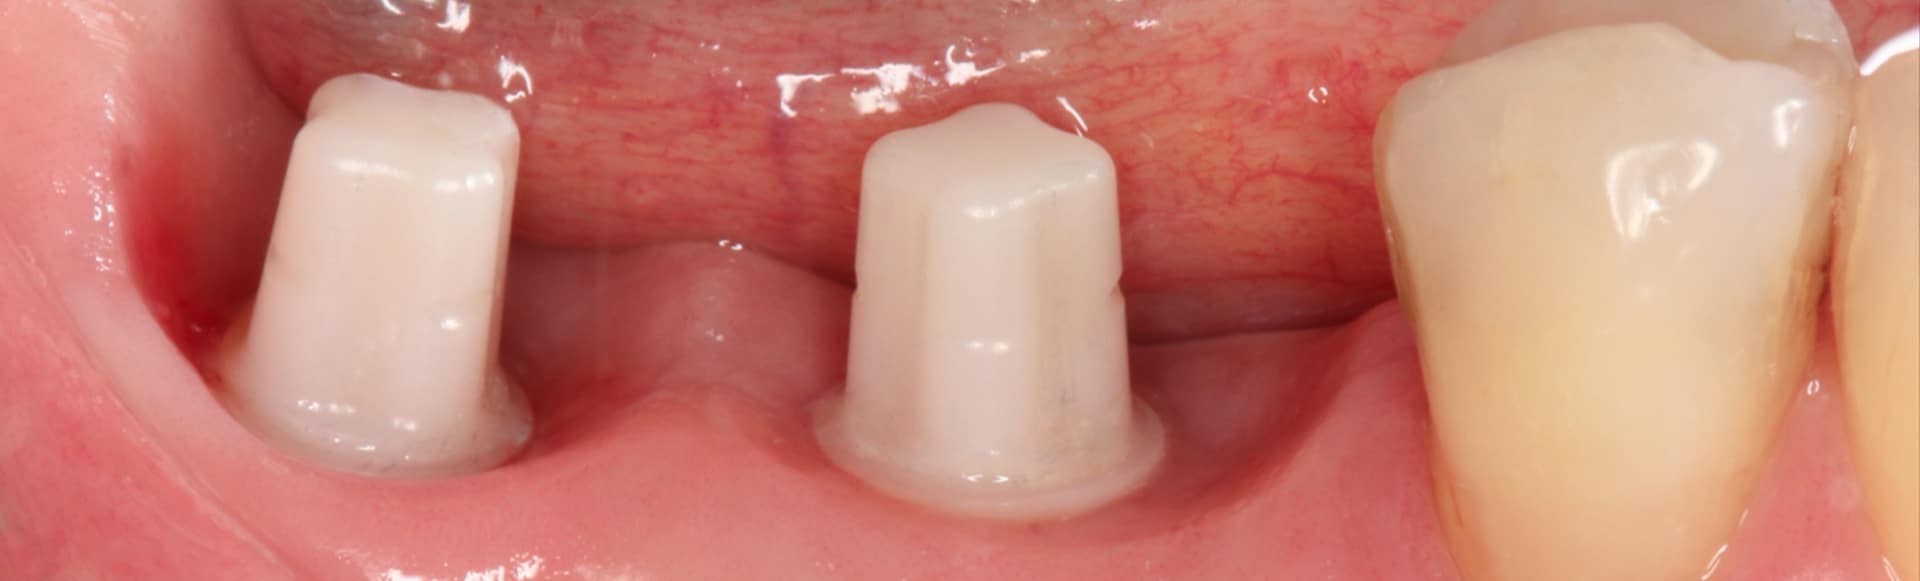

Ceramic implants come with numerous advantages. They closely mimic the appearance of natural teeth, boasting a white color and translucency that makes them virtually indistinguishable and contributes to a beautifully natural smile. Zirconia, the biocompatible material used in ceramic implants, is well-tolerated by the body, reducing the likelihood of allergic reactions or sensitivity and making it an ideal choice for individuals with metal allergies. Ceramic implants provide a holistic and biologically friendly option, ensuring peace of mind for patients concerned about the presence of metal components in their mouths.

Renowned for their exceptional strength and durability, ceramic implants resist corrosion and wear, offering a long-lasting solution for tooth replacement. Additionally, ceramic components on these implants tend to accumulate less plaque compared to traditional metallic components.